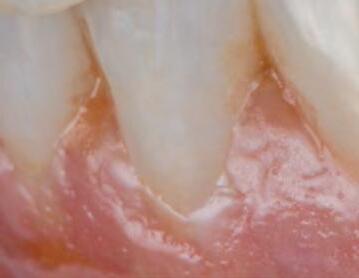

After all, the aesthetic guidelines that hold true for all disciplines in dental technology should, of course, also apply for full dentures: the tooth axes, contact surfaces, angle characteristics, cervical dimension, gingival margin and length-width ratio should be designed like natural dentition. The basic requirement in this respect is a denture tooth that meets aesthetic guidelines and provides an anatomical structure similar to that of natural dentition. And that's the challenge: denture teeth generally – for whatever reason – do not meet aesthetic guidelines and have a lifeless and monotonous appearance when it comes to layering. The vestibular morphology is a flat surface between two ridges without any texture at all, which is why denture teeth of this kind simply cannot offer a natural appearance. The VITAPAN

Bad Säckingen, Germany) denture tooth meets aesthetic guidelines, is layered threedimensionally using enamel, dentin and cervical material, and is pressed from a single mold and cured. The morphology and texture of real teeth was consistently implemented when creating the mould. The following case report demonstrates the resulting benefits, not just in terms of aesthetics but also for setup.

to a more distal position in order to achieve a more individual and natural appearance. The single tooth (46) was enclosed in a circular fashion by the base to provide the upper setup with greater occlusal stability and to compensate for distal movement of the tooth. The patient responded well phonetically and functionally, and was delighted with the natural appearance of the denture teeth. Thanks to the three-dimensional anatomical structure in multiple layers, and the harmonious shade gradient from the neck to the incisal area, the VITAPAN EXCELL anterior tooth set had an incredibly lifelike appearance. Its natural morphology and nuanced surface texture facilitated a brilliant play of shade and light in the patient's mouth, even during try-in. The distinctive incisal characteristics with a white incisal margin and integrated mamelon structure created an organic shade effect, while the balanced light transmission resulted in natural light dynamics.